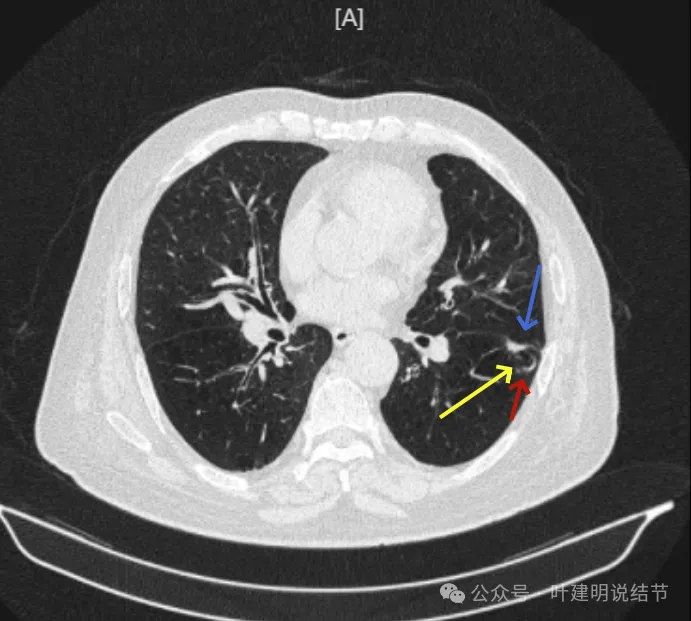

再看2024年9月时的影像:

病灶出现,紧贴叶间裂,有小血管走向病灶侧。

中间有空腔,叶裂侧实性并牵拉叶间裂。

囊腔灶、轮廓清、小血管进入囊壁、囊壁厚薄不均、叶间胸膜牵拉。

表面不平、混合密度、囊腔壁厚薄不均、内壁不光滑、有细支气管扩张通气征。